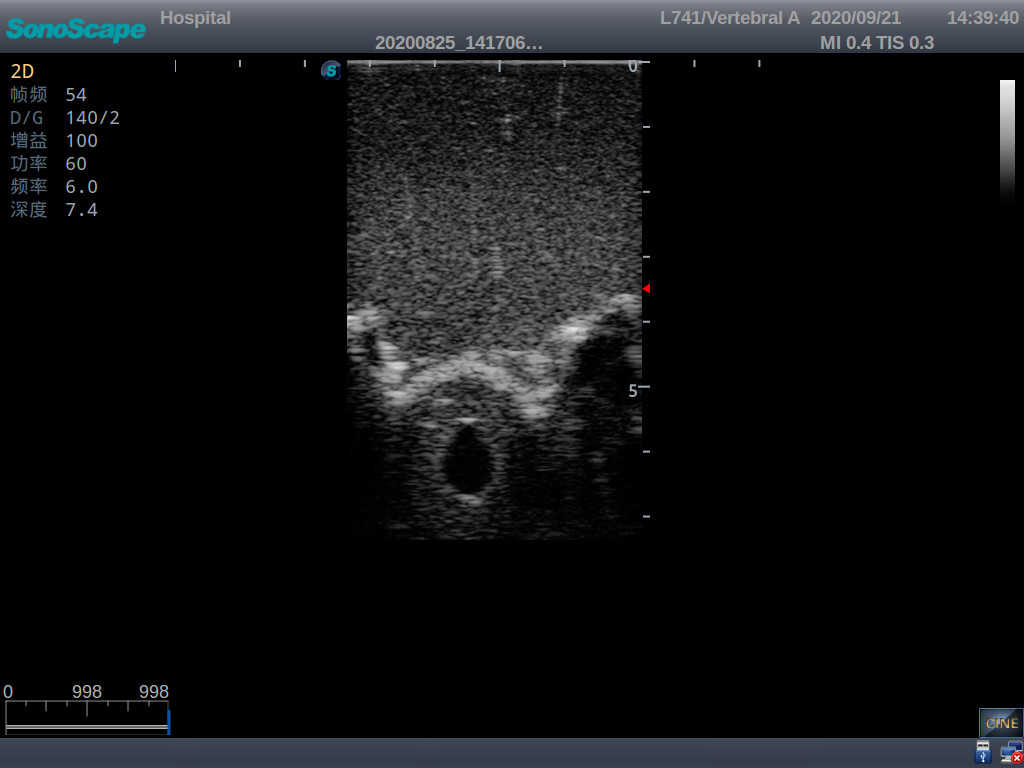

This model is an ideal choice for ultrasound-guided adult lumbar puncture training with true-to-life skin feel and touch, accurate anatomical structures as well as real clinical ultrasound images. Realistic resistance to needle tips and correct landmarks provide excellent hands-on experience.

Accurate anatomical structure of L1-L5 and the vertebral canal

2)  Real clinical ultrasound images

3)  Compatible with various real ultrasound machines

1)   Ultrasound-guided lumbar puncture practice